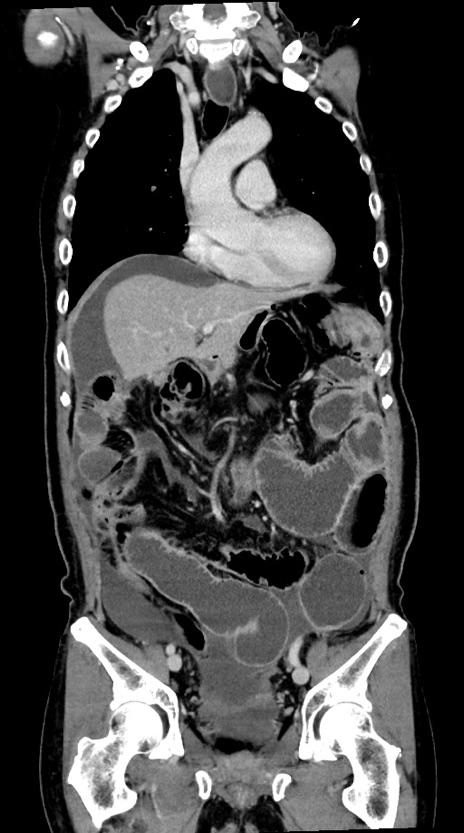

横断像

【症例】60歳代男性

【主訴】嘔吐

【現病歴】胃癌にて胃全摘後。食思不振が悪化し、夜中に嘔吐することがある。

【既往歴】胃癌、胃全摘、脾摘、胆摘後

【データ】WBC 5900、CRP 10.56